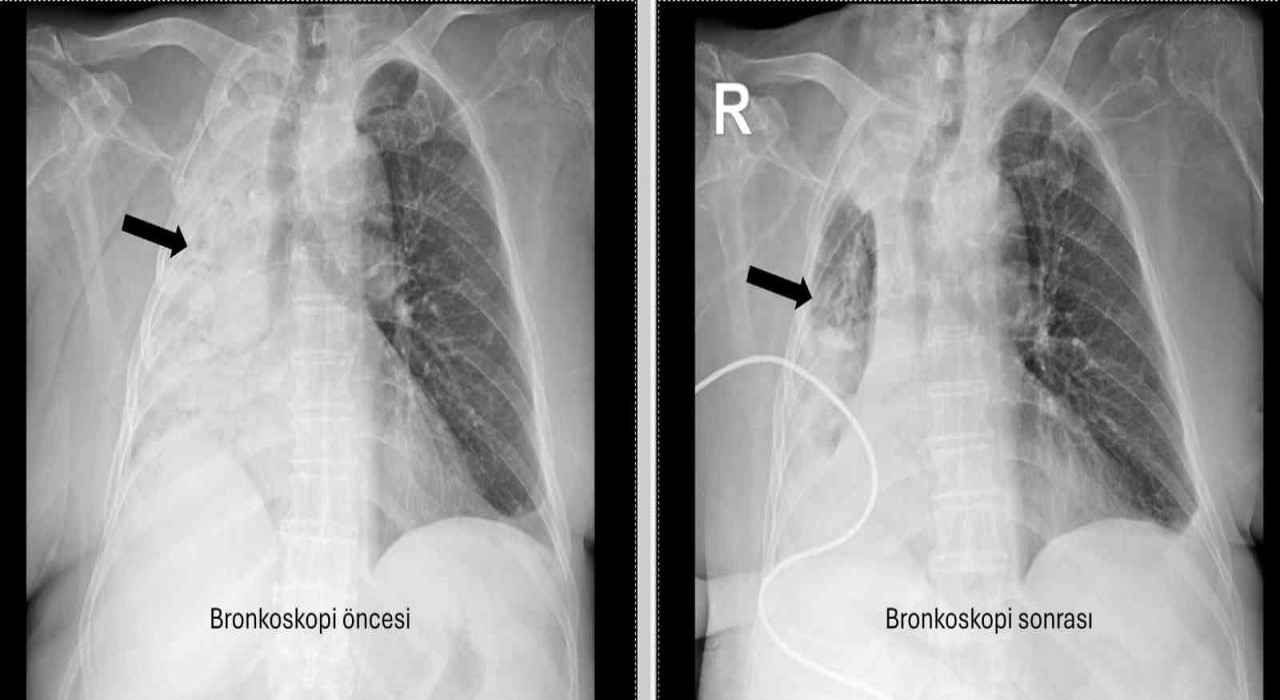

Denizli’de yaşayan ve emekli öğretmen olan 78 yaşındaki felçli kadın son zamanlarda sık sık akciğer enfeksiyonu nedeniyle hastaneye gidiyordu. 1 ay önce gittiği hastanede bronkoskopi yapılmasına rağmen sorun saptanmadığı öğrenildi. Yaşlı kadının son gittiği hastanede sağ akciğerinin tamamen kapandığının tespit edilmesi üzerine Pamukkale Üniversitesi Hastanesine başvuruldu. PAÜ Hastaneleri Göğüs Hastalıkları Anabilim Dalı Öğr. Üyesi Prof. Dr. Göksel Altınışık Ergur, tarafından yapılan tetkiklerde sağ akciğere giden hava yolunun bütünüyle kapalı olduğu görüldü. hastaya acil bronkoskopi planlanıp hemen işlemin gerçekleştirildiğini söyleyen Prof. Dr. Altınışık Ergur, "Fleksibl (esnek, eğilip bükülebilir) bronkoskop ile hava yolları incelenirken çok yoğun ve koyu sekresyon olduğu, bunun iyice temizlenmesi sonucunda ancak hava yollarının incelenebileceği görüldü. Aspiratör (içerideki salgıları emmeye yarayan bir cihaz) sayesinde hava yollarına steril sıvı verilip emilerek bu temizlik yapıldı. Sonrasında sağ akciğere giden hava yolunda sarı bir nesne olduğu görüldü. Bu hâliyle yabancı cisim olduğu anlaşıldığı gibi bunun mısır tanesine benzerliği de açıktı. Yabancı cismi çıkarma işlemi genel anestezi altında, rijit bronkoskop ile yapılmak üzere planlanabilirdi; çünkü bu durumun tedavisi yabancı cismin oradan, ek sorun oluşturmaksızın çıkarmaktı. Ancak, genel anestezi altındaki bir işlem için hastanın genel durumu bozuk olduğundan, özellikle ek hastalıkları ve enfeksiyon varlığı ile işlem riski artacağından hastadaki cismin fark edildiği sırada çıkarılmasına şans vermek daha uygun görüldü. Hava yolu içindeki sıvıları emen aspiratörün gücünü kullanılarak cismin çıkarılması mümkündü. Bronkoskobun ucu, sarı cismin gövdesine dayanıp aspiratör ile emme sayesinde ikisi birbirine sımsıkı yapıştırıldı. Emme gücünün azaltılmamasına dikkat ederek yabancı cisim ve bronkoskop, aynı zamanda hava yollarından dışarıya başarı ile çıkarıldı. İşlem sonrasında hasta yakınına mısır tanesi açısından tıbbi öykü yeniden sorulduğunda, hastamızın bundan beş ay önce yediği pizzanın üzerinde mısır taneleri olduğu öğrenildi. O sırada ani bir yakınma ortaya çıkmadığı için böyle bir ihtimal akla gelmemişti. Düşkün hastalar taneli gıdalar yerken, bu durumun fark edilmeden de gelişebileceğini göstermesi açısından önemli olan bu tablo, hastaların bir dedektif titizliği ile değerlendirilmesi gerekliliğini bir kez daha ortaya koymaktadır" dedi.